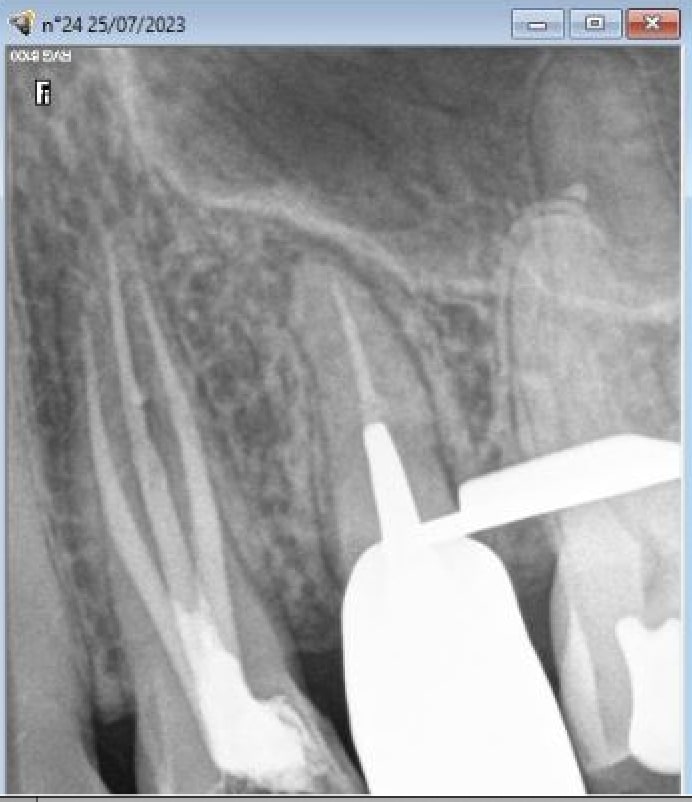

Une histoire de racine fendue ? Tu vois quoi toi, sur les radios ?

J’ai soigné ce patient il y a quelques années. Son praticien a pris sa retraite depuis.

Je lui ai dit qu’il fallait reprendre 25 et extraire 26.

Pour moi c’est perforations, dépassements, fistules, douleurs, poches, furcations, espace biologique, bourrages alimentaire, forme, teinte …

Des radios comme ça on en a tous plein nos tiroirs.

On peut aussi faire comme le cas des 25/26 que j’ai montré, et là c’est pas la même.